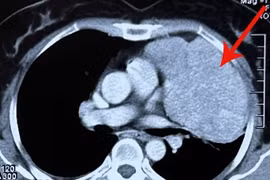

Các bác sỹ khoa Ngoại lồng ngực Bệnh viện K đã tiến hành phẫu thuật thành công, bóc tách khối u kích thước lớn trung thất sau vùng ngực bụng dính vào tĩnh mạch chủ dưới, dính một phần động mạch chủ bụng và phổi phải.

Đau vai gáy 6 năm nhưng chị Vũ Thị Th. (55 tuổi, ở Hưng Yên), nghĩ là do mình làm nghề thợ may, phải ngồi nhiều. Tuy nhiên, khi cơn đau tăng nặng và đi khám, bác sĩ chẩn đoán bệnh nhân bị u trung thất trước kích thước lớn xâm lấn tim và phổi.

Lần đâu tiên bệnh viện Phổi TƯ đã phối hợp cùng Bệnh viện E sử dụng hệ thống máy tim phổi nhân tạo (hệ thống tim phổi ngoài cơ thể) để cắt khối u trong ngực cứu bệnh nhân bị u trung thất ở phía sau tim.